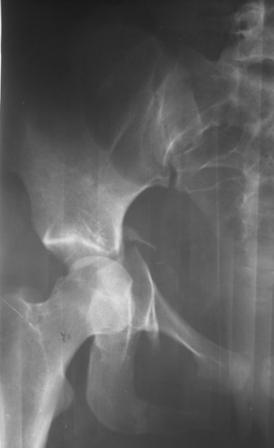

30/11/04 |  30/11/04 |  30/11/04 |  14/12/04 |  14/12/04 |  14/02/05 |  14/02/05 |  21/02/05 | Уважаемые коллеги! Случилось вторичное смещение вертлужной впадины после операции. Посоветуйте, что делать. Пациентка 18 лет. Травма 19.11.04. D.s.: Закрытыый Т-образный высокий перелом правой вертлужной впадины. Закрытый перелом м\мыщелкового возвышения левой б\берцовой кости. 9.12.04 операция - открытая репозиция, остеосинтез переломам вертлужной впадины. 30.12.05 выписаны на амбулаторное лечение с рекомендациями не вставать на правую ногу. 14.02.05 при контрольном осмотре на Р-граммах выявлено вторичное смещение передней колонны. Клинически подвывиха нет, имеется умеренная приводящая контрактура правого тазобедренного сустава, гипотрофия мышц н\конечностей. Госпитализирована в травмотделение. Выполнено КТ. Имеется смещение передней колонны кнутриЮ диастаз 8 мм. Посоветуйте пожалуйста, что предпринять в данной ситуации.

Сустав-то как раз неплох, поскольку впадина почти вся конгруэнтна, по крайней мере вся нагружаемая часть, и подвывиха бедра нет. Артроз в перспективе тут, конечно, не исключить, но на первом плане проблема целости тазового кольца, т.е. нестабильное несращение, о чем А. Рунков писал. На седалищной дефект, и если и разошедшееся основание лонной не срастется, то болезненные проявления могут быть сразу после начала нагрузки, как ее не отсрочивай.